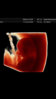

Wow spennandesHer er våre to små 8+4. Verdens fineste overraskelse. Den ene er 1,75 cm og den andre er 1,55cm. To bankende hjerter og begge bevegde seg![]()

Veldig spennende!! Skalp ny ultralyd på fredag. Veldig spent på om begge har utviklet seg i riktig retningWow spennandes![]()